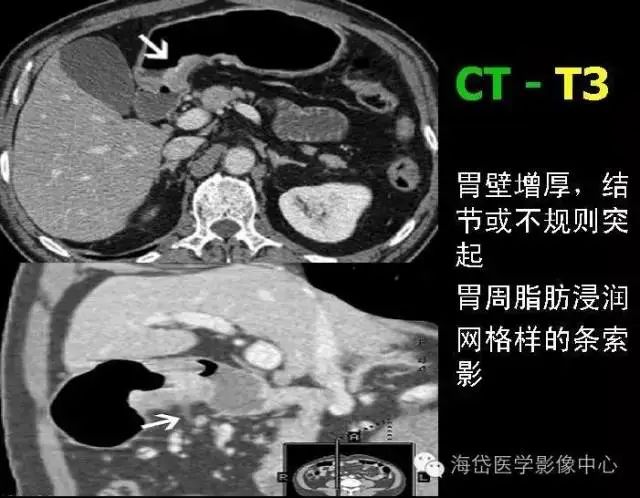

T——原發腫瘤 Tx:原發腫瘤無法評價; T0:無原發腫瘤的證據; Tis:高度異型增生,局限于上皮內,未侵犯固有層; T1:腫瘤侵及黏膜固有層或黏膜下層 T1a 腫瘤侵及黏膜固有層;T1b 腫瘤侵及黏膜下層; T2:腫瘤侵及固有肌層; T3:腫瘤侵及漿膜下層; T4:T4a 腫瘤侵透漿膜;T4b 腫瘤侵及鄰近器官。